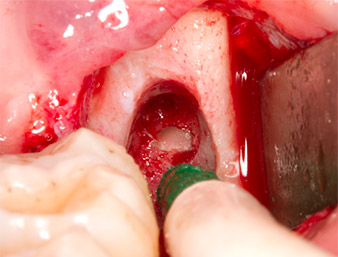

Granulation tissue

Fig. 4: Two Langenbeck retractors and a raspatorium expose the operating area. Granulation tissue of the incompletely healed first osteotomy can be seen.

The tissue above the root remnant was not completely ossified and consisted for the most part of granulation tissue modified by inflammation (Fig.4).